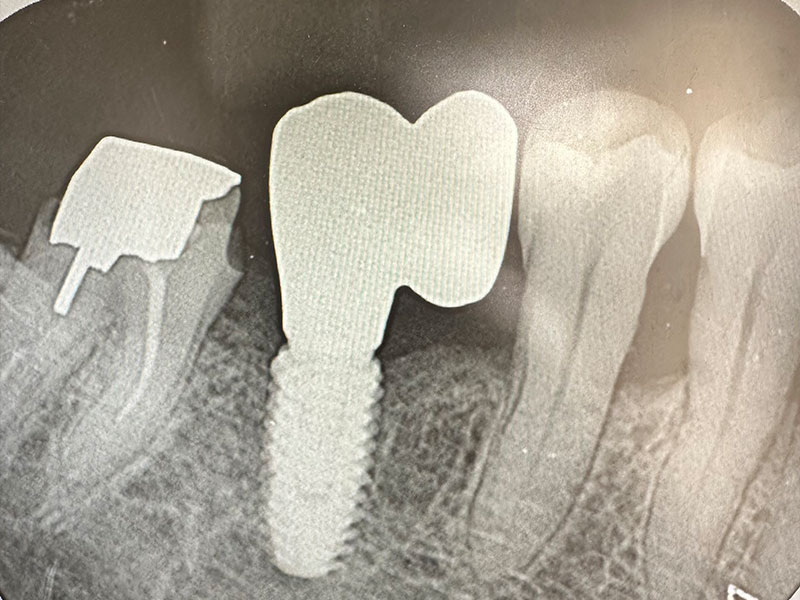

レントゲン写真およびCT画像なのですが、右上6が残歯状態であり歯根破折を起こしている状態でした。しかし歯槽骨から上顎洞底までの距離は十分に認められます。この歯槽骨から上顎洞までの距離がないとソケットリフトなどのオプションの処置が必要になってくるのですが、今回の症例では大掛かりな処置の必要はなく症例の難易度としては比較的イージーな方でした。上顎洞などに関して知りたい方はこちらのページを参照にしていただければと思います。

インプラント埋入手術

インプラントの埋入に関しては1回法で行いました。抜歯した部位の骨はしっかりと治癒していました。インプラント埋入後はヒーリングキャップと言ってインプラント周囲の歯茎の形態を整えるためのキャップを装着しました。手術時は特に大きな問題はなく無事に手術が終了しました。

インプラント上部構造装着

インプラントの上部構造と言って、インブラントの「歯」に核当する部分を装着しました。隣在歯との歯にも調和しています。患者様にも咬みやすいと喜んでいただくことができました。

インプラントの埋入に関しては1回法で行いました。抜歯した部位の骨はしっかりと治癒していました。インプラント埋入後はヒーリングキャップを装着しました。手術時は特に大きな問題はなく無事に手術が終了しました。インプラントの露出を避けるためにも骨幅が少しでも広いところに埋入するために理想的な位置よりは少し後ろになっています。

インプラントの上部構造を装着しました。インプラント部の清掃性を考え、小臼歯が2つ並んだような形態にしました。こちらの形態の方が歯間ブラシが通しやすくインプラントが長持ちします。